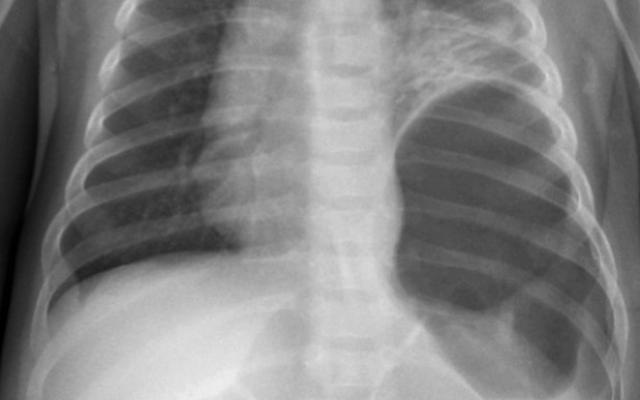

Een 3,5 maanden oud meisje, met een blanco voorgeschiedenis, werd verwezen naar de SEH vanwege een plotseling ontstane kreunende ademhaling. Wij zagen een wakker, bleek meisje met een kreunende ademhaling zonder verdere tekenen van verhoogde ademarbeid. De saturatie was 93-95%, zonder extra zuurstof. Over de longen hoorden we verminderd ademgeruis links, met links basaal-ventraal darmgeluiden in de thorax; over de buik hoorden we spaarzame peristaltiek. De lever was 5 cm onder de ribbenboog palpabel. Aanvullend werd een thoraxfoto gemaakt. Deze liet onverwachts een hernia diaphragmatica links zien met een gevulde dikkedarmlis in de thoraxholte en een verplaatsing van het…